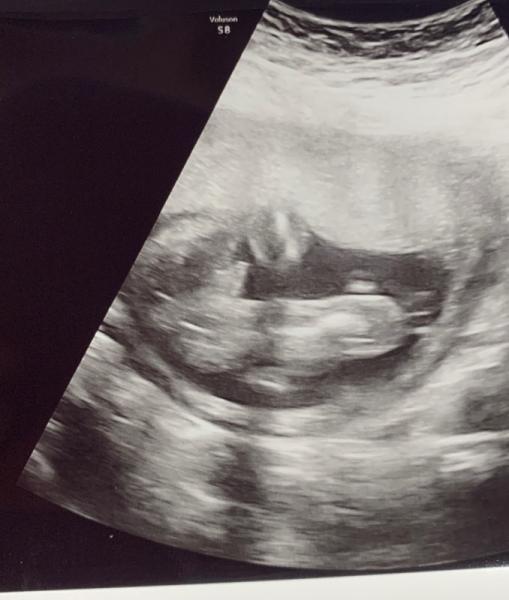

Hallo Ich bin in der 18 ssw und mein Frauenarzt hat mir eine Tendenz zu einem Jungen gegeben. Was meint ihr ?

Bild zu

Würde auch eher Junge sagen. Ich war vor 1 Woche beim 2. Trimester Screening bei 19+6 und der Arzt gab mir das Bild mit. Was würdet ihr sagen?

Ich würde auf junge tippen. Hast du keine Tendenz bekommen?

Doch der Arzt meinte es könnte ein Junge werden aber er konnte im US nichts definitives darstellen.